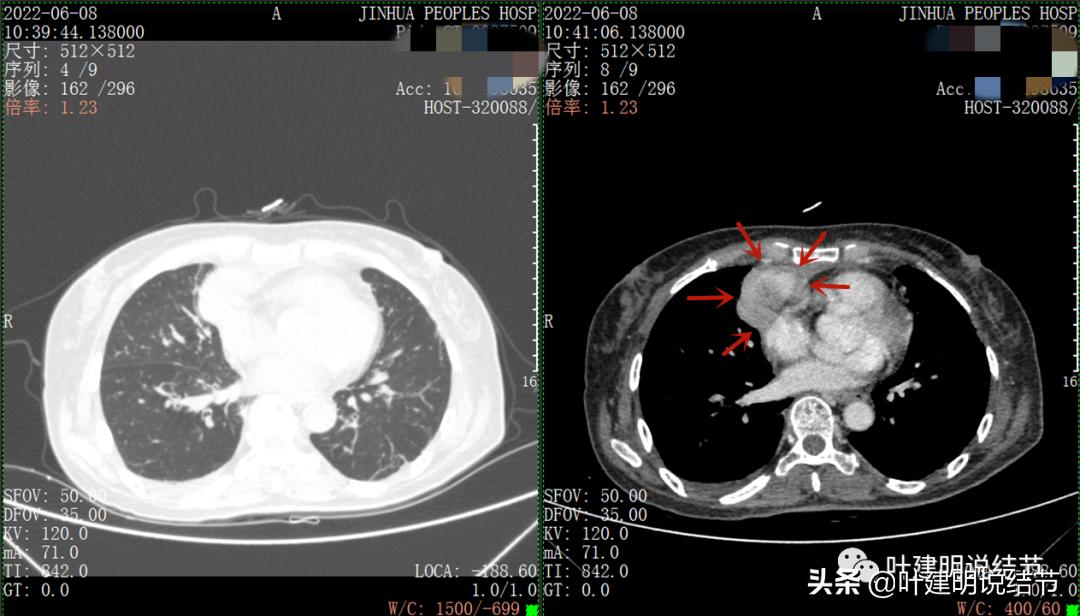

以下图片左侧是肺窗,右侧是纵隔窗。红色箭头示病灶,桔色箭头示无名静脉,黄色箭头示支气管,砖色箭头示上腔静脉,蓝色箭头示主动脉,紫色箭头示肺动脉。

绿色箭头示近膈面处,心脏边病灶

此灶与主病灶不是完全相连的

病灶占据前纵隔从上到下全程,多中心,密度不均,对心脏与大血管有压迫,没有明显侵犯

病灶表面不平,中间有坏死